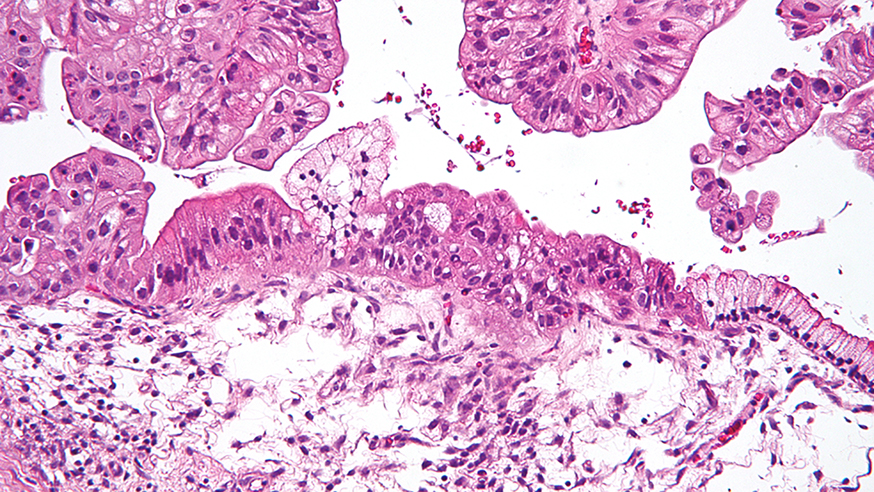

Intermediate magnification micrograph of a low malignant potential (LMP) mucinous ovarian tumour